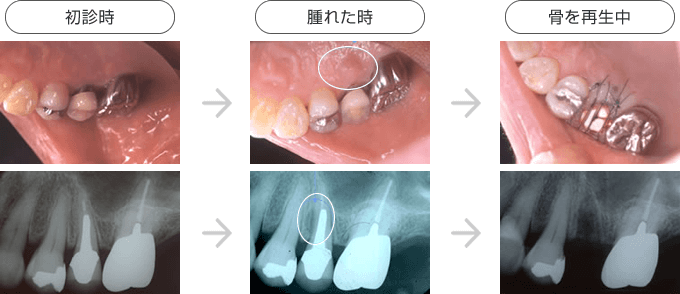

歯周病等で骨が失われた部位に人工骨や自家骨 (自分の骨) を移植し、骨の再生を図る治療のことで、歯周組織再生療法のひとつです。GBRは主に「インプラントしたいけれど骨の量が足りない」場合に行います。